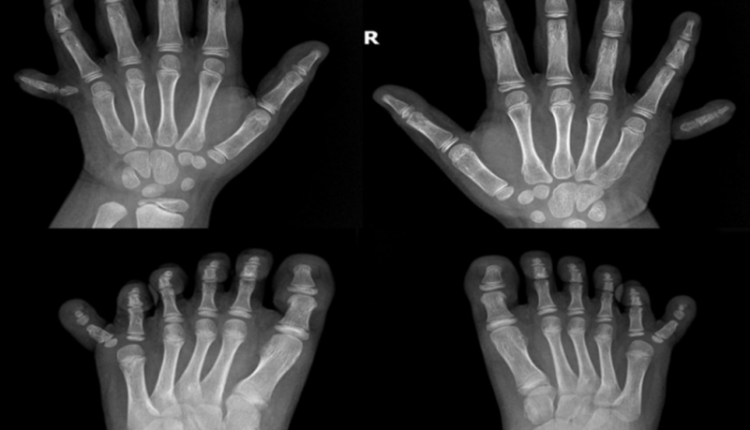

Bé Trang (7 tháng tuổi, ngụ Long An) đến phòng khám Ngoại Nhi BVĐK Tâm Anh TP.HCM trong tình trạng bàn tay và bàn chân bị dư ngón phức tạp. Cụ thể, ngón út trên bàn tay trái và phải bé thừa một mẩu thịt nhỏ, ngón cái bàn tay phải tách làm đôi, bàn chân phải có 2 ngón cái, ngón cái và ngón trỏ bàn chân trái dính nhau gần hết. Tổng cộng, hai bàn tay chân của cháu có 24 ngón thay vì 20 như bình thường.

BS.CKII Nguyễn Đỗ Trọng thông tin, dựa trên vị trí của ngón thừa trên bàn tay/bàn chân, y khoa chia dị tật thừa ngón thành 3 loại: thừa ngón về phía trong (phía xương quay cẳng tay hay xương chày cẳng chân): ngón thừa nằm ngoài ngón cái, thừa ngón về phía ngoài (ngón thừa nằm ngoài ngón út) và thừa ngón trung tâm (ngón thừa nằm giữa các ngón khác). Một số ngón thừa chỉ là da và mô mềm nhô ra từ bàn tay/bàn chân. Trong khi đó, có trường hợp ngón phụ cũng có da, mô mềm và xương khớp tương tự như một ngón tay/chân bình thường. Cá biệt, có trường hợp các ngón tay/chân dính nhau một phần hoặc toàn bộ, gây khó khăn cho trẻ trong sinh hoạt và vận động. Trường hợp của bé Trang là dị tật thừa ngón về phía trong, xảy ra ở ngón tay cái.